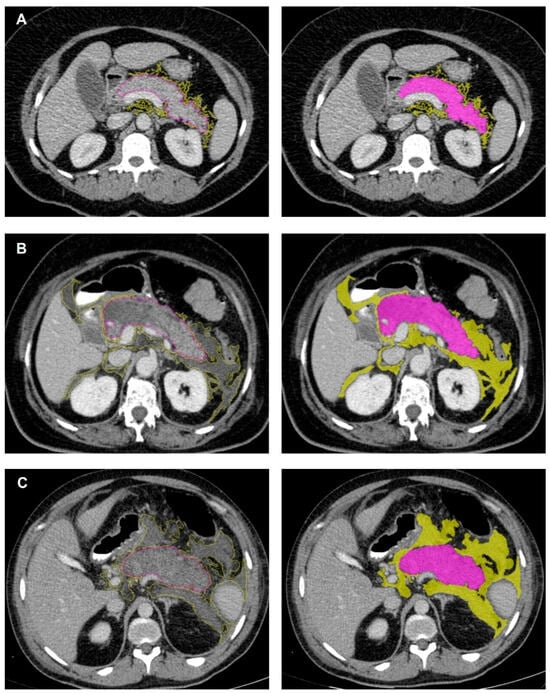

2.3. CT Image Interpretation and Feature Extraction